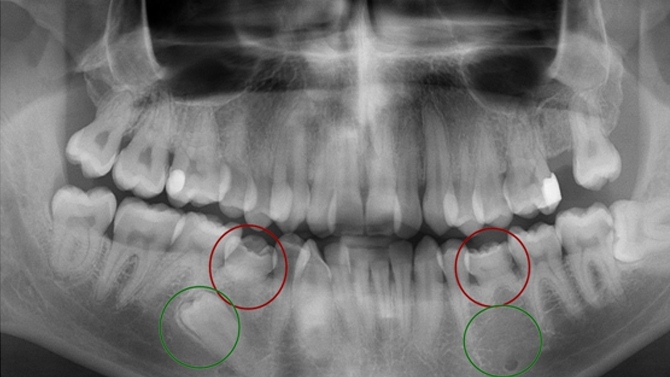

Como puedes observar en la siguiente imagen, los círculos rojos corresponden a la dentición temporal (dientes de leche) del paciente, y los círculos verdes a los dientes definitivos, en la parte izquierda el diente de leche tiene sucesor, mientras que en el otro lado existe una agenesia.